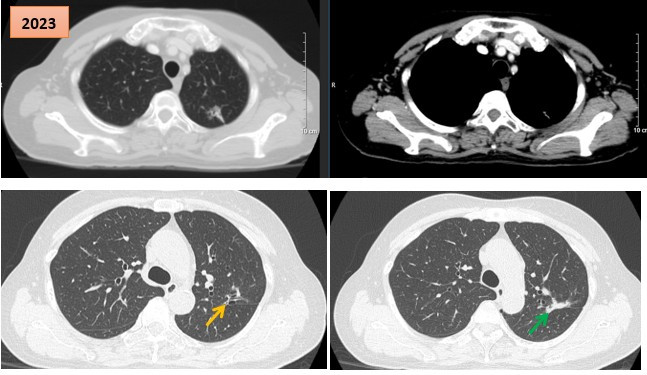

Thứ Sáu, ngày 30/01/2026 10:04Các bác sĩ Trung tâm Y học hạt nhân và Ung bướu (Bệnh viện Bạch Mai) vừa ghi nhận một trường hợp bệnh nhân ung thư phổi giai đoạn muộn được điều trị bằng thuốc TKIs thế hệ I từ năm 2017...